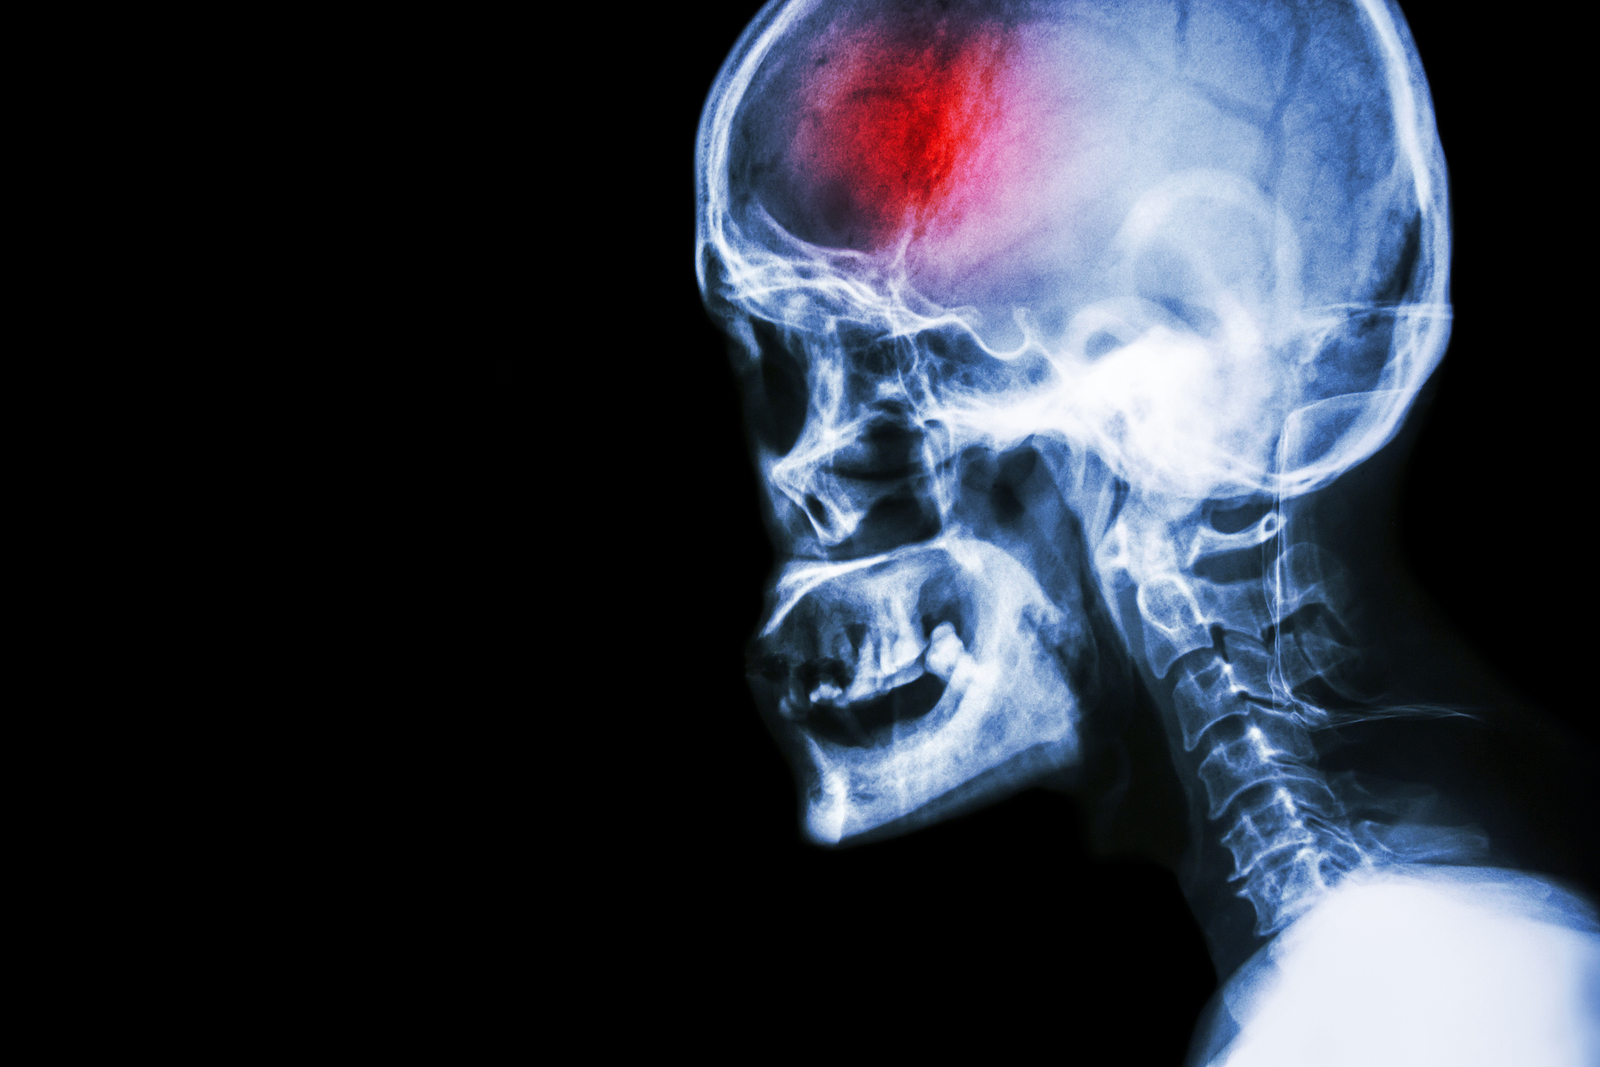

A stroke (previously known as a cerebrovascular accident) when there is a decreased flow of blood to the brain from either a blockage in the blood vessels that supply the brain (ischemic stroke), or a bleed from the blood vessels that supply the brain (hemorrhagic stroke). When the blood flow to the brain is blocked it prevents the brain from getting the needed oxygen and nutrients to function. Without oxygen the brain cells can be permanently damaged or die and the physical and mental functions related to that area of the brain will be affected. A stroke is a medical emergency and rapid treatment is crucial to decreasing the damage caused by a stroke.

- Ischemic stroke: a stroke that is caused by a blockage (clot) that disturbs the blood flow to the brain.

- Hemorrhagic stroke: a stroke that is caused by a bleed that disturbs the blood flow to the brain and puts pressure on the surrounding tissue.

- Transient ischemic attack: often referred to as a “mini-stroke” or TIA, where the blood flow to the brain is temporarily disturbed and as a result causes temporary signs and symptoms of a stroke that resolve quickly .

Computed Tomography (CT) scan and/or Magnetic Resonance Imaging (MRI) scan: These tests are done on your brain and used to locate the exact location of the stroke and to determine if it has been caused by a blockage or a bleed. These tests can also help rule out other conditions that may be causing symptoms, such as an infection or a brain tumour